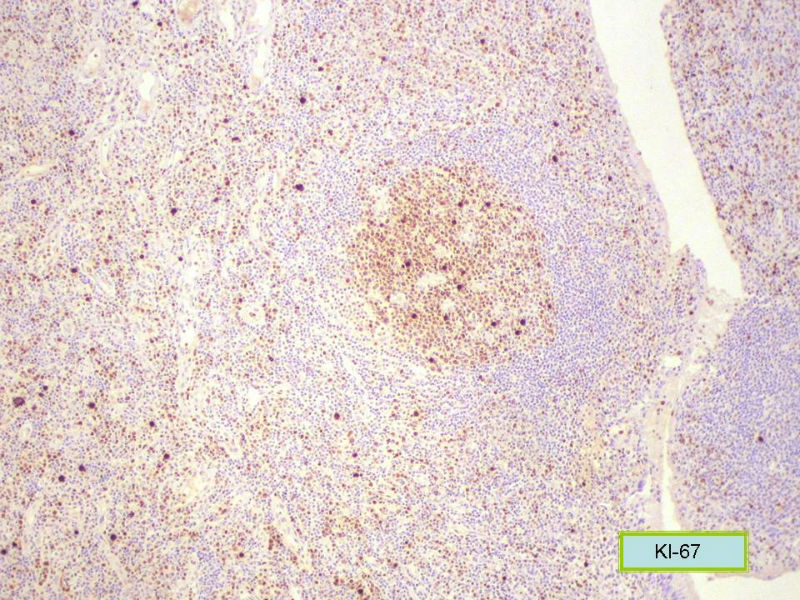

Ki-67标记在淋巴滤泡(生发中心)细胞全阳性,而且显示出生发中心边缘规则,不像是肿瘤,呈反应性增生。

Ki-67标记在滤泡间和淋巴组织弥漫增生区见散在阳性细胞,这些阳性细胞可能是转化性淋巴细胞,有的甚至是内皮细胞或组织细胞。